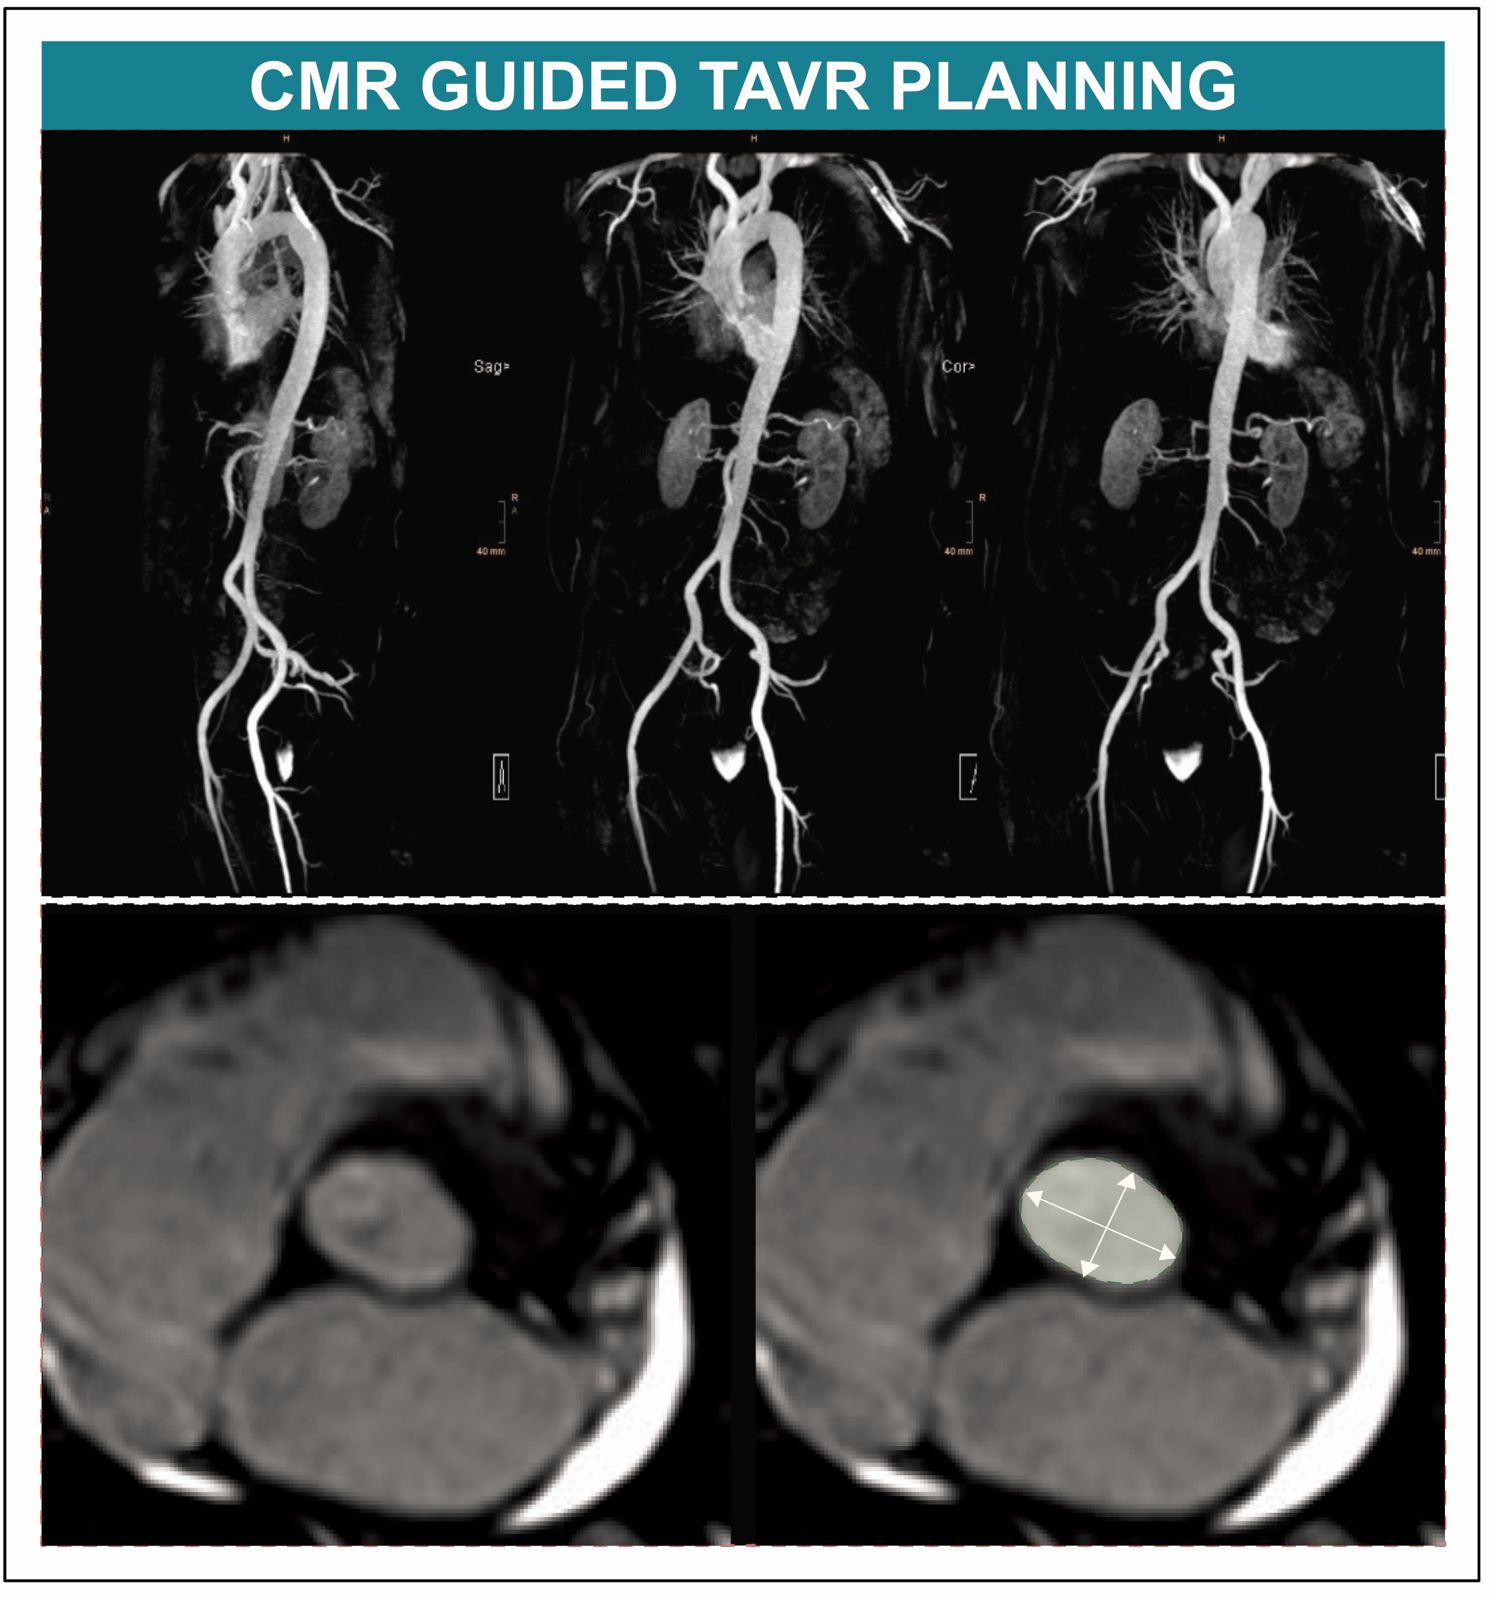

Die prä-interventionelle Planung des Eingriffes erfolgt üblicherweise mittels Computertomografie (CT), was für PatientInnen mit Niereninsuffizienz aufgrund des erforderlichen Einsatzes von iodhaltigem Kontrastmittel allerdings eine wesentliche Einschränkung darstellt. „Rund die Hälfte aller TAVI-Kandidatinnen und -Kandidaten leidet an einer Niereninsuffizienz und ist durch den Einsatz jodhaltiger Kontrastmittel im Rahmen einer CT einem erhöhten Risiko für eine Nierenschädigung ausgesetzt. Die Strahlenbelastung im Rahmen des CTs ist ein weiterer Nachteil, vor allem im Lichte der immer jünger werdenden TAVI-Population“, weiß Sebastian Reinstadler von der Innsbrucker Univ.-Klinik für Innere Medizin III (Kardiologie und Angiologie). Agnes Mayr von der Innsbrucker Univ.-Klinik für Radiologie ergänzt: „Die kardiale Magnetresonanztomographie (CMR) bietet sich als vielversprechende strahlenfreie Alternative an, bislang fehlten jedoch randomisierte Daten zum Vergleich der Tauglichkeit von CMR- und CT-gesteuerter TAVI“.

BU: Neue Daten belegen, dass die Kardioale Magnetresonanztomografie bei der Planung einer TAVI keine Nachteile hat. (c)Kardiologie Innsbruck

In einer neuen, kürzlich im anerkannten Fachjournal Circulation veröffentlichen Studie konnte nun erstmals die CMR als gute und klinisch geeignete Alternative für die TAVI-Planung nachgewiesen werden. Für das Kooperationsprojekt zwischen der Univ.-Klinik für Kardiologie und Angiologie und der Univ.-Klinik für Radiologie wurden TAVI-KandidatInnen an den Herzzentren in Innsbruck und Wels randomisiert und einer CMR-gesteuerten oder einer CT-gesteuerten TAVI-Planung zugeführt. „In der Kohorte mit jenen PatientInnen, die sich einer TAVI unterzogen hatten, konnten wir feststellen, dass die CMR-gesteuerte TAVI der CT-gesteuerten TAVI im Hinblick auf den Implantationserfolg nicht unterlegen war und daher als Alternative zur TAVI-Planung in Betracht gezogen werden kann“ bestätigt Erstautor Martin Reindl, der diese positiven Erkenntnisse gemeinsam mit der von Bernhard Metzler geleiteten Arbeitsgruppe Kardio-MRT am diesjährigen ESC Kongress, dem weltweit führender Kongress im Bereich Kardiologie, in der prominenten "Late Breaking Science" Session vorstellen konnte.